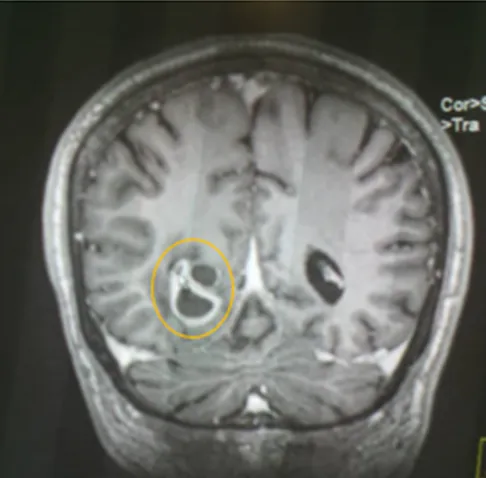

• En vista de compromiso Neurológico se solicita Resonancia Magnética Cerebral donde se evidencia:

Conclusiones del estudio Rx

En el presente estudio se observan múltiples imágenes quísticas de neurocisticercosis, de diferentes tamaños y en diferentes fases, vesicular, nodular y calcificadas, siendo la de gran tamaño la de localización parieto occipital derecha, con importante edema perilesional que genera efecto de masa desplazando estructuras y comprimiendo ventrículos.

En vistas de hallazgo de estudio de neuroimagen, es valorado por el ser servicio de neurología, quienes concuerdan que dichas lesiones son características de Neurocisticercosis, en sus diferentes etapas, siendo la de mayor tamaño de localización parieto occipital derecha en fase calcificada pero con importante edema perilesional.